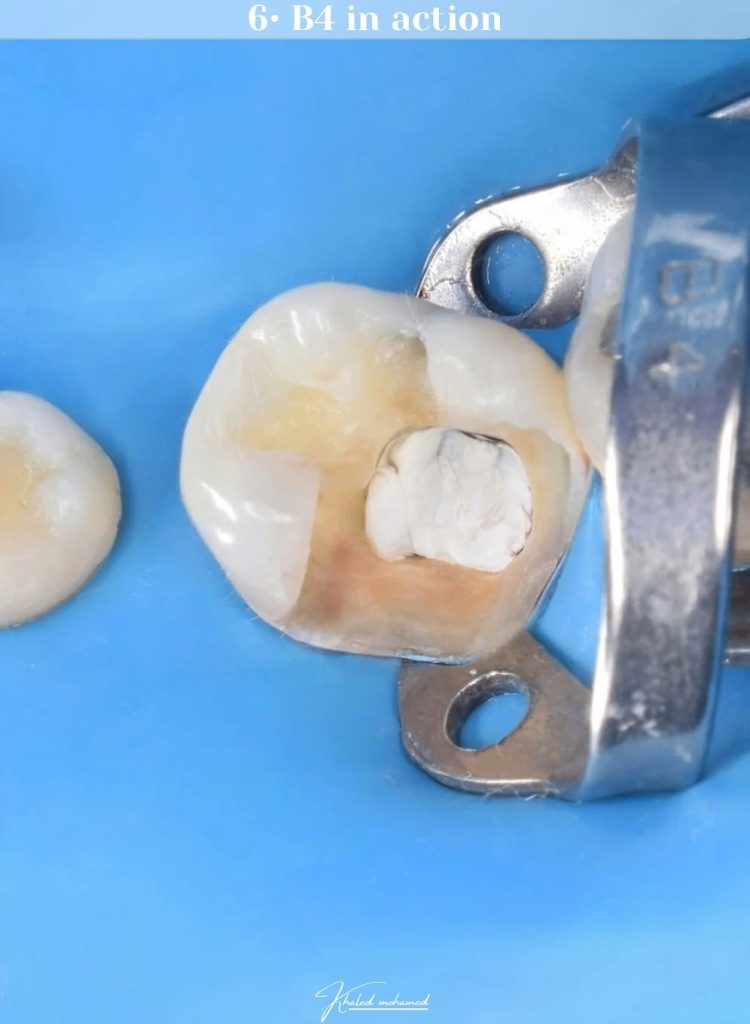

B4 in action

Pre endo build up